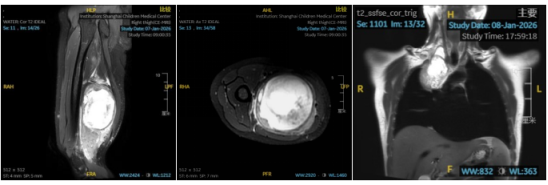

然而,疾病并不会因经济原因而停滞。两个月前,小曦的右腿开始出现乏力与麻木,行走也变得困难。这时,他才意识到问题的严重性,立即前往医院检查。磁共振检查结果令人震惊--他的右大腿后部长出了一个约194.2×84.7×89.1mm的巨大肿瘤,同时右侧胸腔也发现类圆形肿块。

近日,在上海儿童医学中心肿瘤外科顾松教授团队的共同努力下,小曦的右大腿肿瘤被成功完整切除,且血管和神经未受任何损伤。术后病理结果显示,他患的是丛状神经纤维瘤,并且部分肿瘤已出现恶性变迹象。

·精准手术切除:在大腿部位,医生成功切除一个约20×9×9厘米的巨大肿瘤,术中严格保护周围神经和血管,术后患者的腿部感觉和运动功能完全恢复正常;